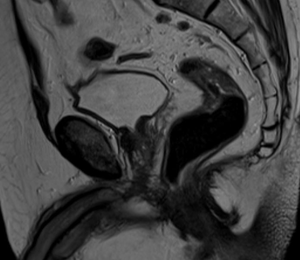

МР-диагностика рака шейки матки